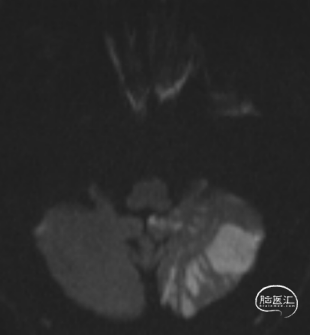

术后头晕呕吐,当日DWI:左侧小脑梗死,MRA未见明显大血管栓塞。